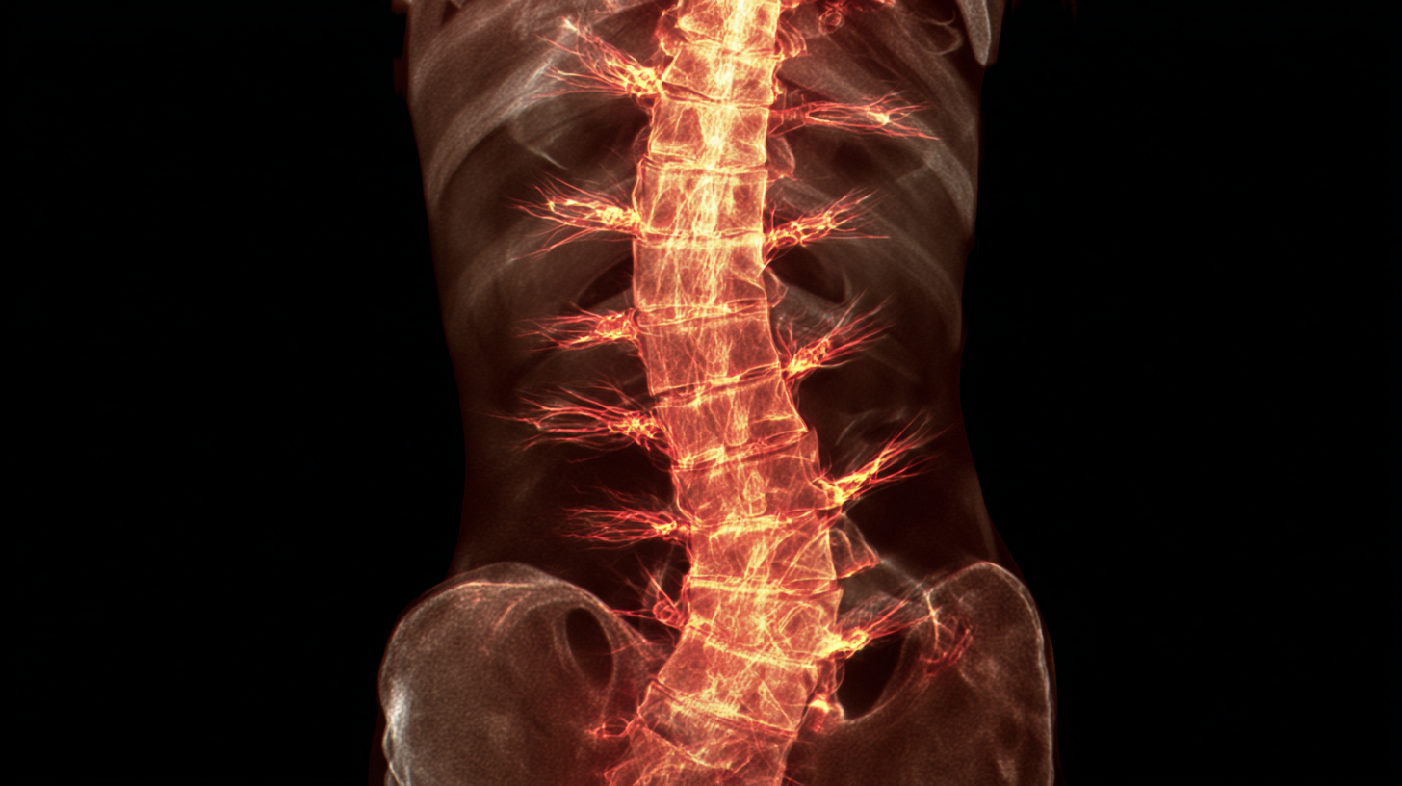

КТ (компьютерная томография):

это метод образования изображения, который использует рентгеновские лучи для создания детальных срезов органов и тканей. КТ также может помочь визуализировать гемангиому и ее окружающие структуры.